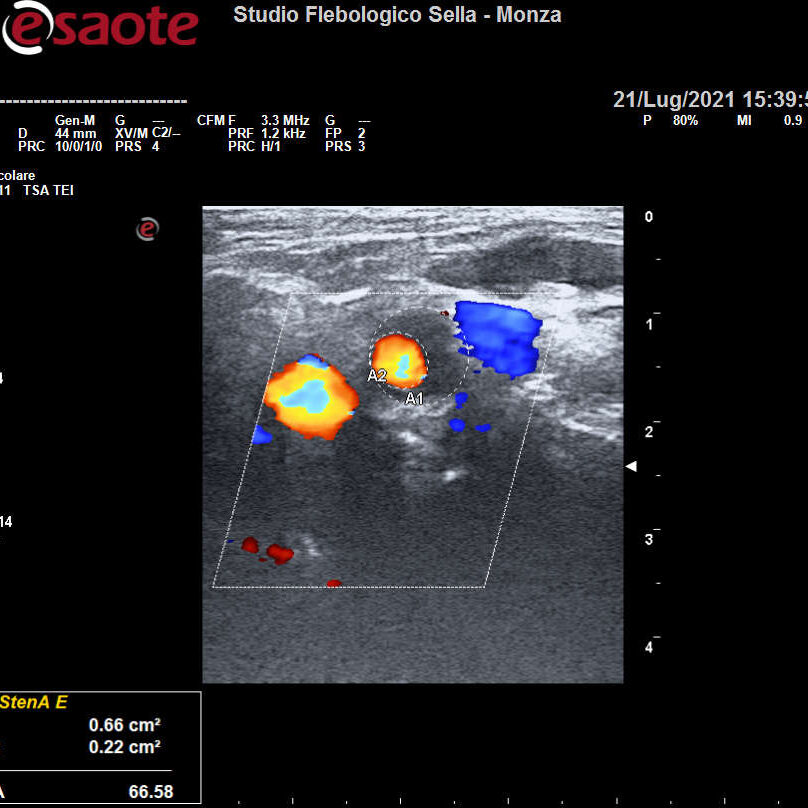

Abbiamo precedentemente visto come l’intuizione del fisico austriaco Christian Doppler ha posto le basi teoriche per la nascita dell’EcocolorDoppler. La deformazione degli ultrasuoni nell’attraversare il corpo umano consente la ricostruzione in immagini dei tessuti, vasi compresi. Otteniamo quindi informazioni sulla forma e il decorso dei distretti vascolari esplorati e sulla velocità del sangue contenuto. Un utile campo applicativo è rappresentato dall’EcocolorDoppler dei tronchi sovraortici ossia lo studio delle arterie del collo. Il precoce riscontro di problemi a carico di carotidi e vertebrali ne previene infatti una grave complicanza: l’ictus ischemico.